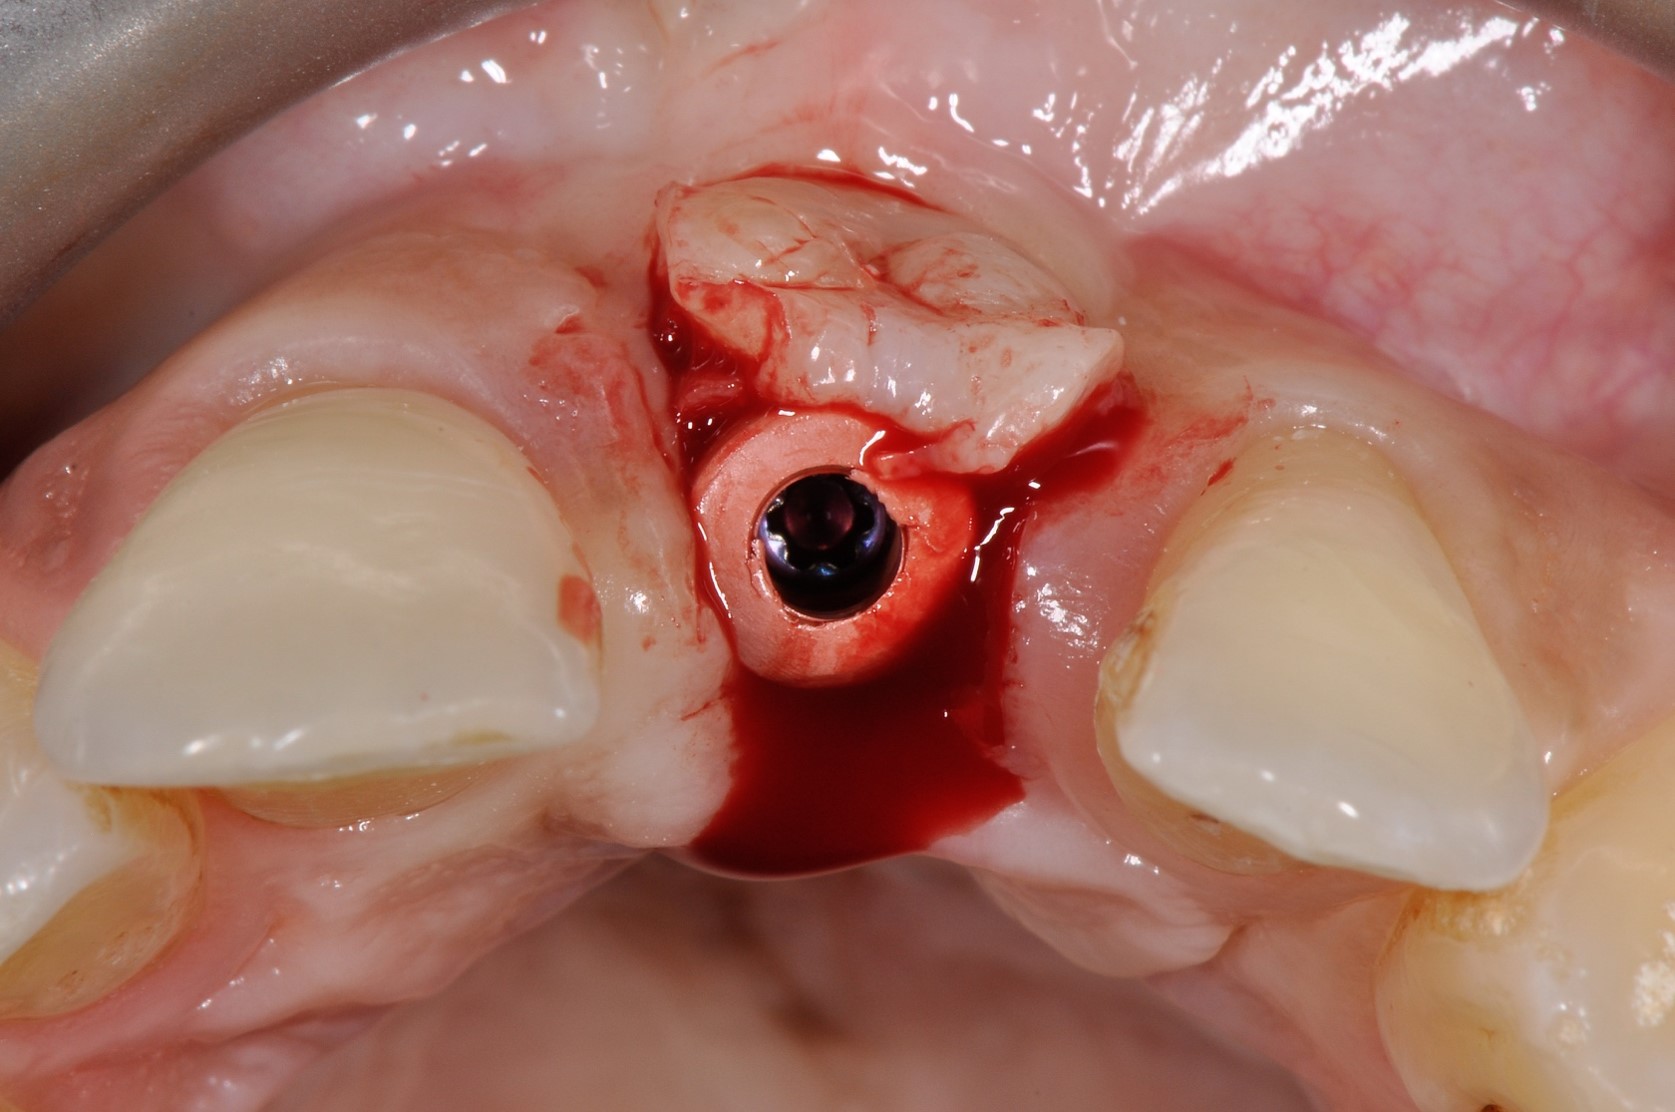

Immediate implant placement with cerabone® and mucoderm® - Dr. F. Rossi - Vestibular wall defect visible after extraction of tooth 11Immediate implant placement with cerabone® and mucoderm® - Dr. F. Rossi

Intact socket following atraumatic tooth extraction